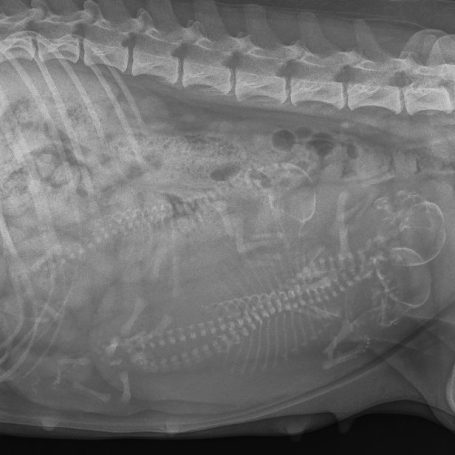

We zijn voor de röntgenfoto geweest en.....wellicht zit er een klein extra pupje in haar buik. Nog even geduld tot de bevalling